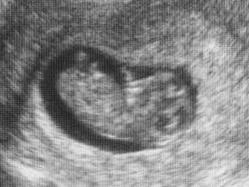

takže teď okolo vánoc přijde ms a pak se vrhneme na úporné snažení a doufám, že se budu taky brzy pochlubit obrázky z utz 😵

@zelvik Asi rosteme, dovnitř nevidím 🙂 Už ale vypadá jako regulérní miminko 🙂